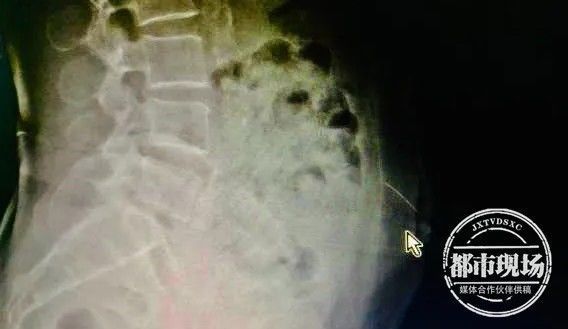

医生:我们也挺惊讶,一般人很少会帮自己针灸,而且第二个,断了针之后,她自己有勇气去割开一个小口想把针拿出来。入院后,医生第一时间通过拍片发现,针还在梁婆婆腹壁里。由于针灸用针又细又长,稍有不慎可能扎到腹腔内脏器,带来严重危害。为了确认针的位置,尽快把针取出,医生对患者做了CT定位和三维重建,发现针已从皮下组织扎到了腹直肌里,万幸未伤及内脏。

确定针的位置后,医生迅速为梁婆婆施行介入手术,通过垂直面向下切开2厘米,成功将断针从腹中取出。随后,医生还给梁阿婆打了破伤风针。目前,梁阿婆已平安出院。但由于针扎的位置就在包块处,阿婆的感染可能要面临更久的愈合期。